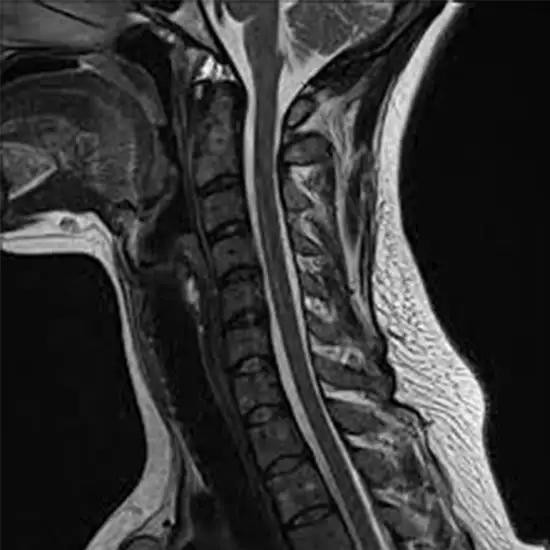

mri cervical spine with contrast

A cervical MRI creates a precise image of your neck spine. It adds information to pictures. Before or during the surgery, contrast is injected.